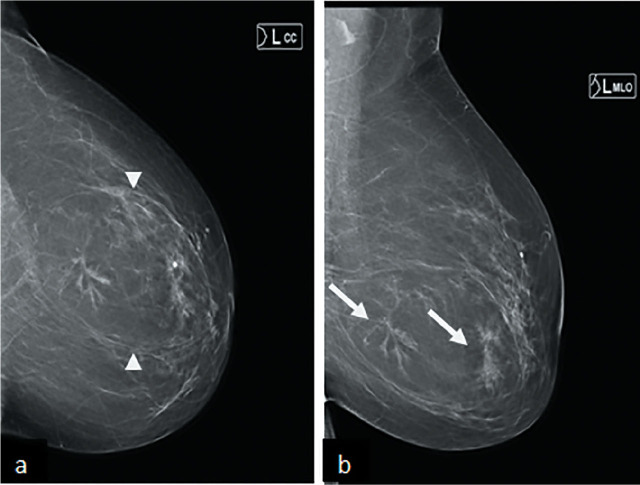

Case description: We present two cases of breast hamartoma in 51 and 61 years old female who presented to us through screening and symptomatic clinics.Both cases had imaging findings typical for diagnosis of hamartoma however there was a distortion within the hamartoma which raised possibility of malignancy and prompted a core biopsy and MDT discussion.